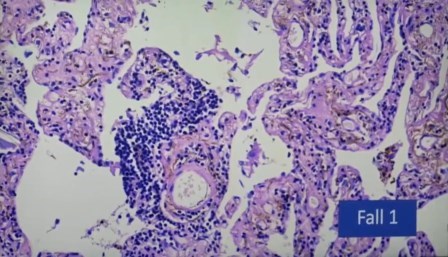

Vasos sanguíneos, endotelitis

El endotelio es la capa que recubre los vasos, son tan pequeños que normalmente no se ven.

Linfocitos en endotelio, endotelitis

Foco de infección, inflamación no sólo de los vasos sanguíneos, sino múltiple.

Aglomeración de linfocitos alrededor de un vaso

«Esto no es autolisis y lo vemos una y otra vez, con desprendimiento del endotelio de los vasos, entotelitis», exclama el científico. Terrible.

«Antes no lo había visto, y yo he visto mas de 40 mil autopsias y 500 mil biopsias, estas células que se han desprendido no es autolisis, porque hay también eritrocitos, que son las células largas, y no pueden estar allí después de la autolisis y lo vemos una y otra vez. Hay desprendimiento de células endotélicas», detalla.